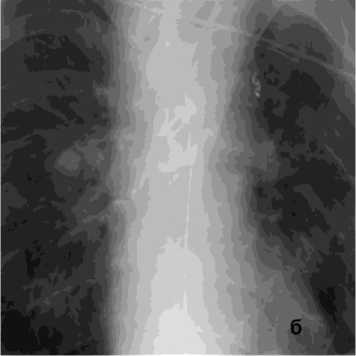

В общей сложности погибло два пациента с аорто-бронхиальными свищами и ЛК3Б. Причиной кровотечения в одном случае у пациентки 86 лет явилось расслоение грудного отдела аорты с прорывом в бронх, в другом – у пациентки 31 года после трансплантации лёгких, стентирования стриктуры левого долевого бронха вызвало в последующим пролежень аорты. После эпизода массивного ЛК пациентам проведён полный комплекс гемостаза, включая стентирование аорты (1), санацию трахеобронхиального дерева (2), бронхоблокацию, на фоне ИВЛ (2) (рис. 9, б).

Рисунок 9. Аортография у пациента после трансплантации лёгких, ЛК 3Б: а – аорто-бронхиальный свищ с поступлением контраста в левый главный бронх; б – эндопротезирование нисходящего отдела аорты протезом Ankura TAA2622B160 – без признаков экстравазации

Figure 9. Aortography in a patient after lung transplantation, PH grade 3B: a – aortobronchial fistula with contrast extravasation into the left main bronchus; б – endovascular repair of the descending aorta with Ankura TAA2622B160 stent graft – no signs of extravasation